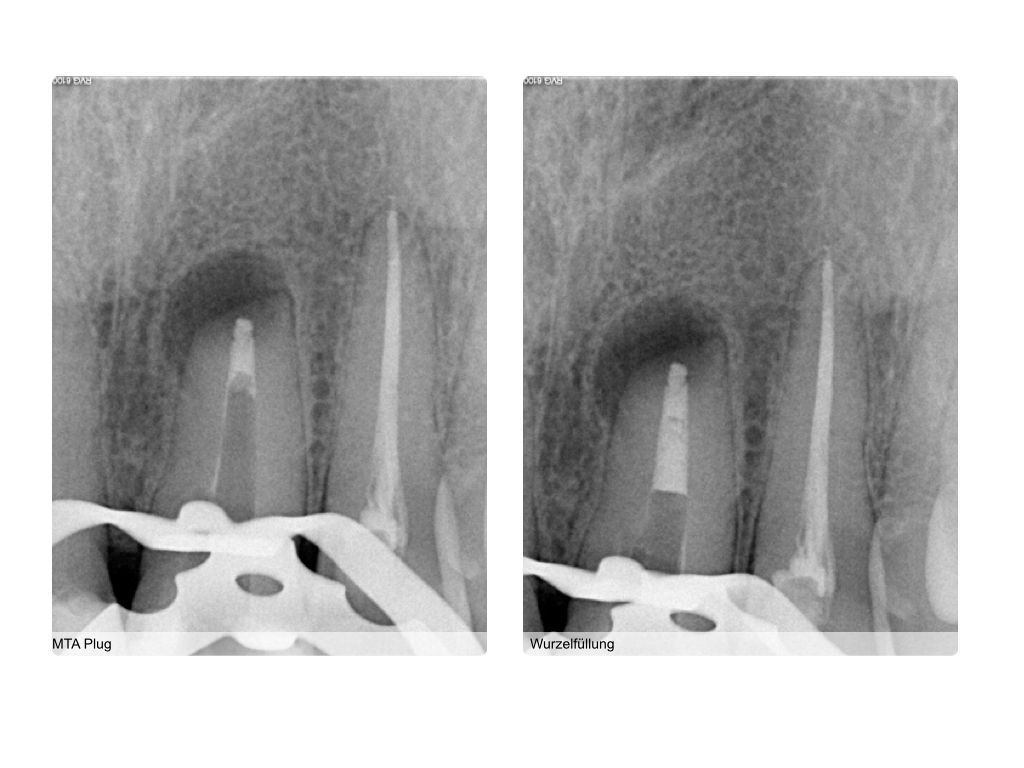

Z.n. WSR